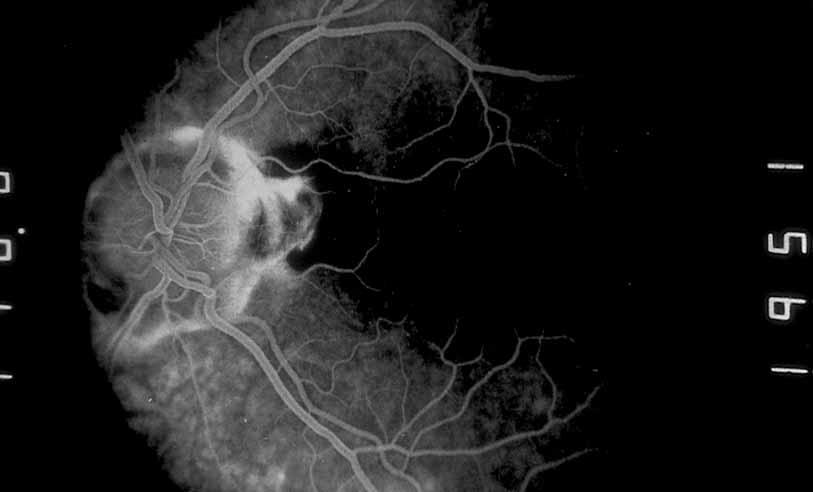

A third instance in which fluorescein angiography concentrating on the optic nerve may be helpful is in eyes with vascular engorgement of the optic nerve, especially with media opacities. Fluorescein angiography may help the clinician distinguish abnormally leaking capillaries from neovascularization. In acute multifocal hemorrhagic retinal vasculitis, optic nerve involvement is common in the early stages of the disease, 47 with optic nerve disc neovascularization seen later (see Figs. 10, 11, 12, and 13). Another fluorescein angiographic clue to the distinction between optic disc vessel engorgement and true neovascularization is the presence of associated large zones of retinal capillary nonperfusion such as those seen in sarcoidosis (see Figs. 14 and 15),34–40 acute multifocal hemorrhagic retinal vasculitis (see Figs. 10 and 11),47 or Eale disease (see Figs. 16 and 17).48–52

Fig. 12 Acute multifocal hemorrhagic retinal vasculitis. The patient later developed disk neovascularization with vitreous hemorrhage. Note the areas of neovascular leakage from the optic nerve.